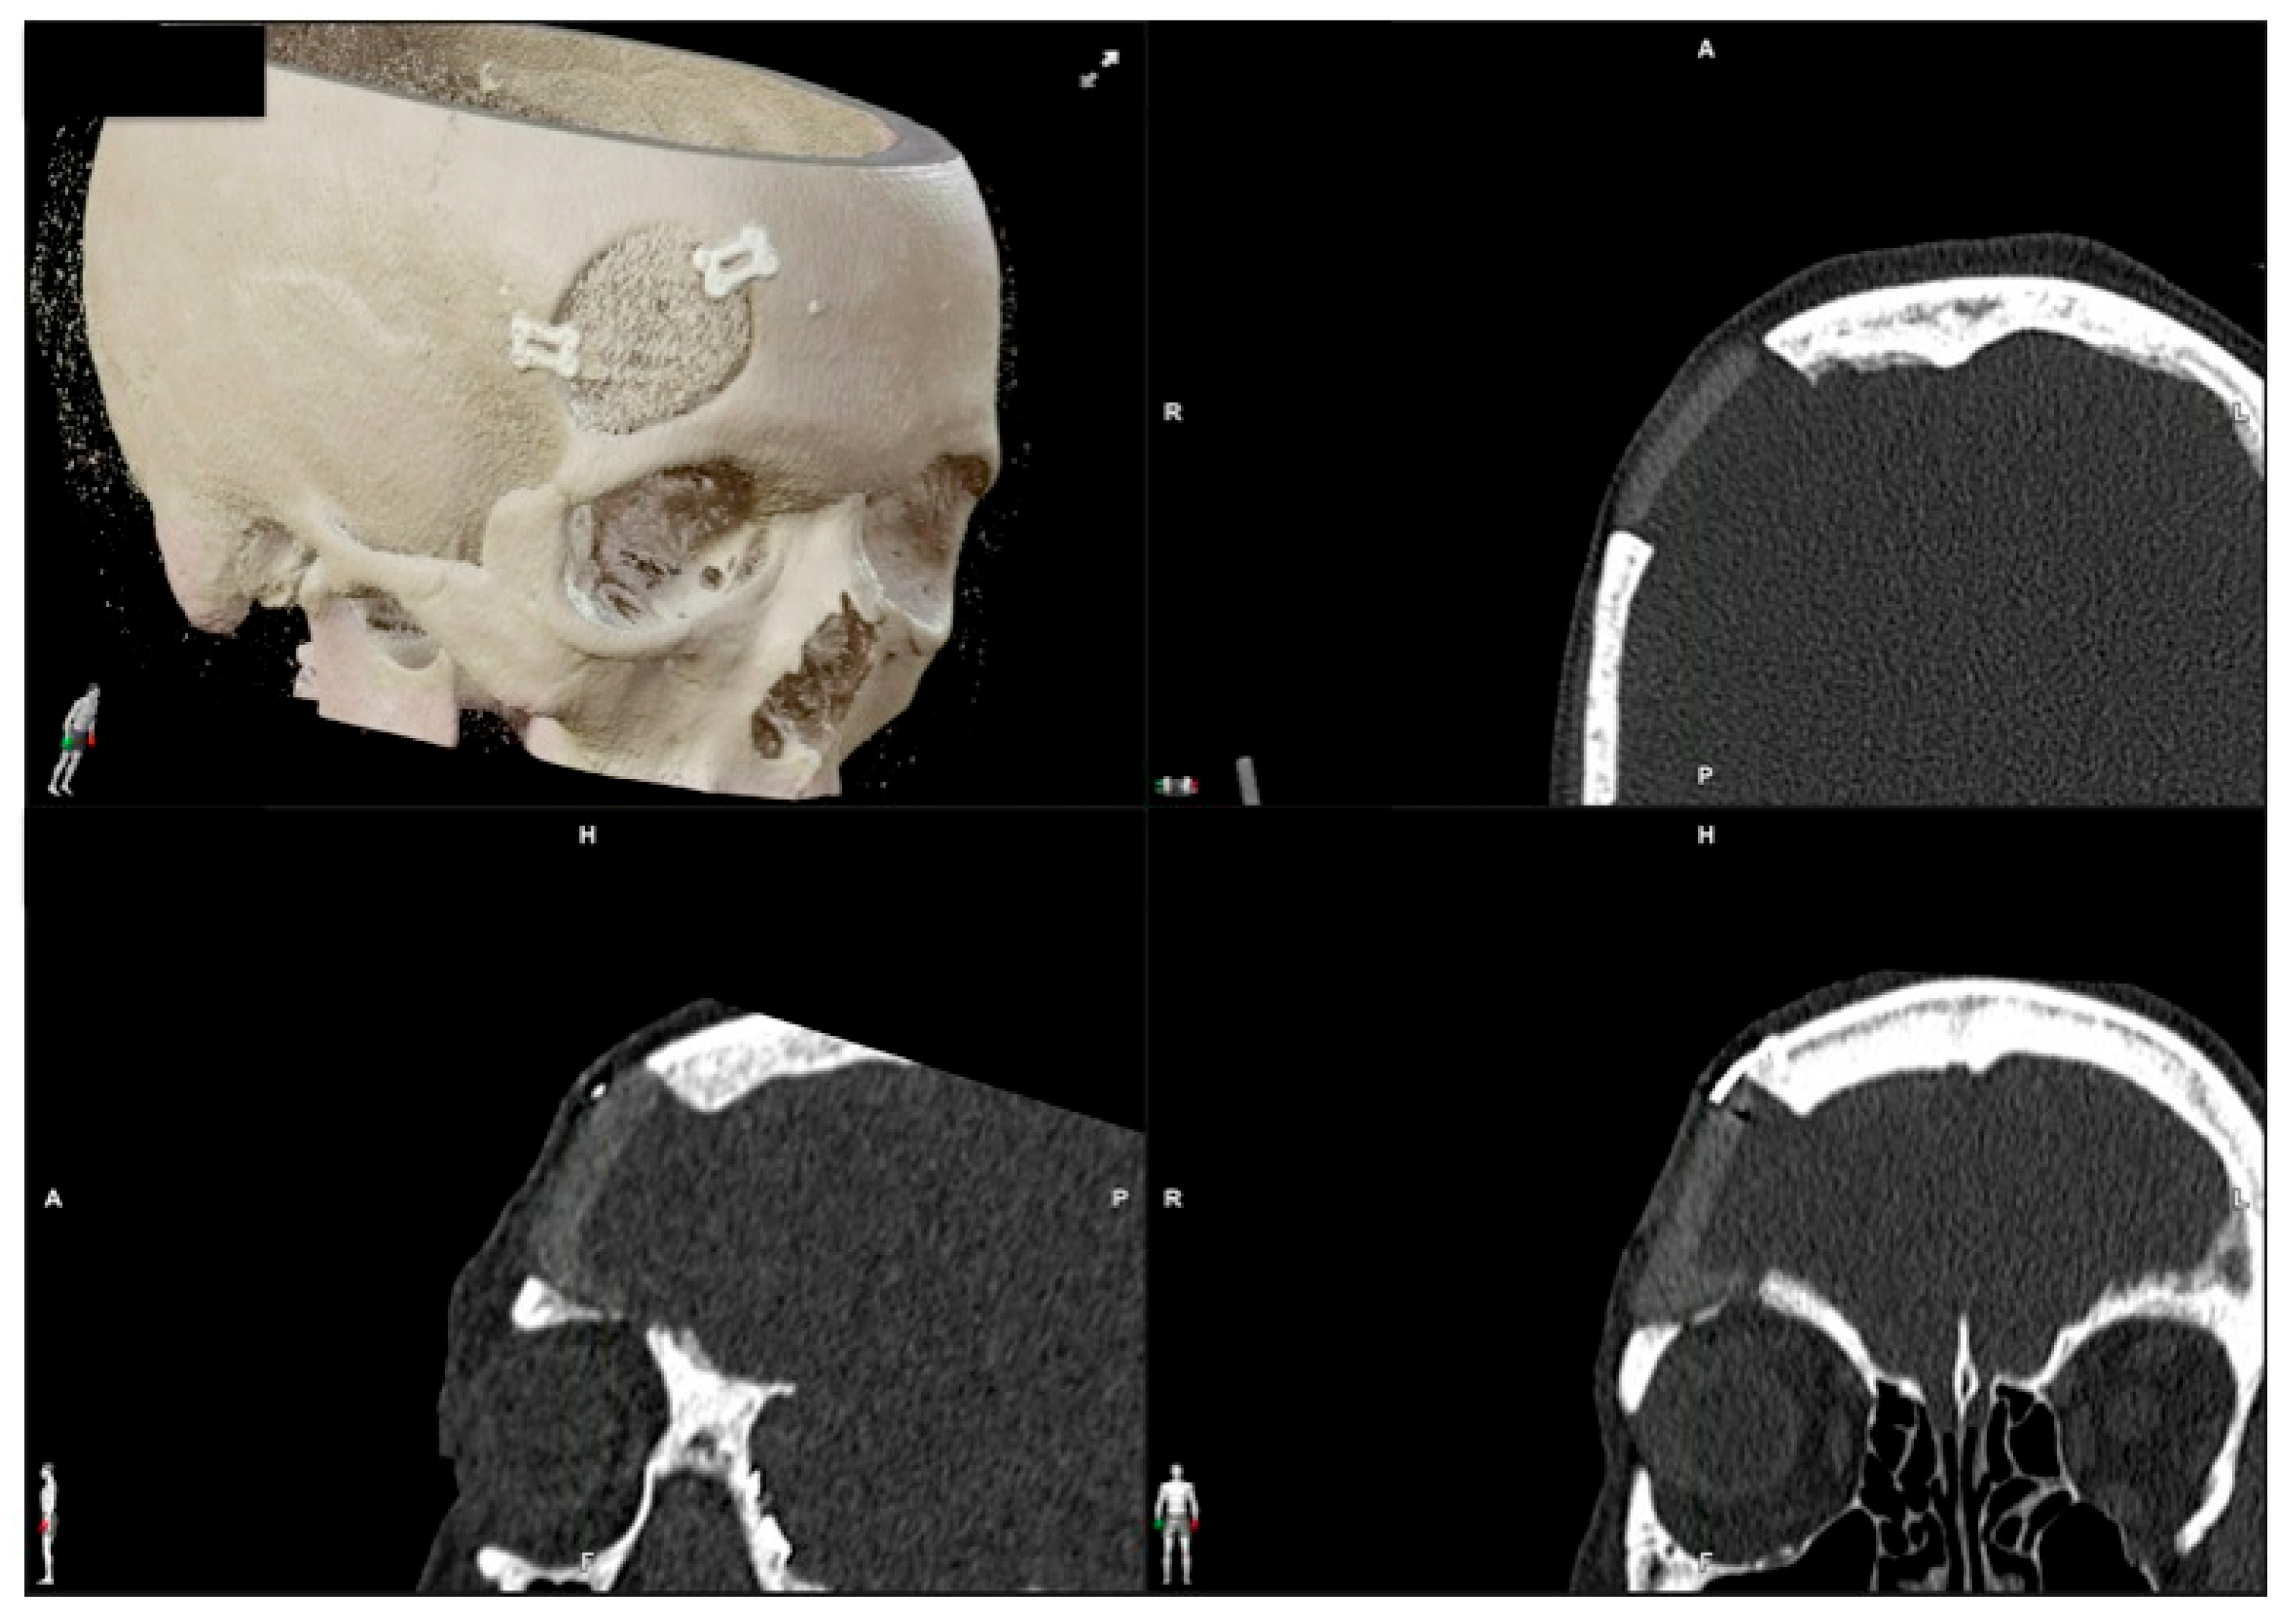

| 1 | 53/F | L/25 mm | Y | 4 mo | Dystopia | N | CT, MRI | Supraorbital rim, orbital roof | Intraosseous venous malformation | - | Resection + reconstruction | Y | Y | 1st, 2nd, 3rd | Coronal | Y | Piezoelectric device | N | PEEK prosthesis | 7 y/N |

| 2 | 54/F | R/33 mm | Y | 9 y | N | Y | CT, MRI | Frontal bone, orbital roof | Intraosseous venous malformation | - | Resection + reconstruction | Y | Y | 1st, 2nd, 3rd | Coronal | Y | Piezoelectric device | N | PEEK prosthesis | 6 y/N |

| 3 | 36/F | L/19 mm | Y | 6 mo | N | N | CT, MRI | Zygoma | Arteriovenous malformation | - | Resection + reconstruction | Y | Y | 1st, 2nd, 3rd | Transconjunctival + blepharoplasty + maxillary vestibular | Y | Piezoelectric device | N | PEEK prosthesis | 5 y/N |

| 4 | 47/M | L/30 mm | N | 2 y | N | N | CT | Zygoma | Intraosseous venous malformation | - | Resection + reconstruction | Y | Y | 1st, 2nd, 3rd | Transconjunctival + lateral canthotomy + maxillary vestibular | Y | Piezoelectric device | N | PEEK prosthesis | 6 y/N |